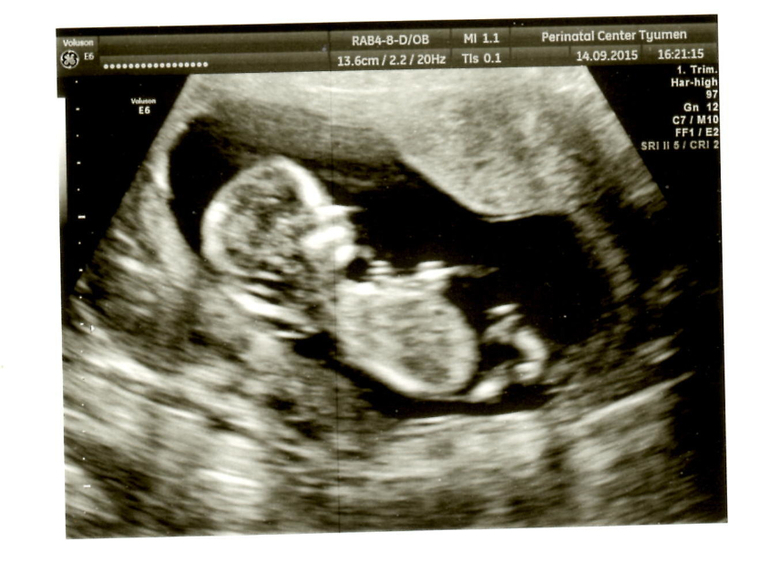

Вот и состоялась снова наша встреча с малышом)) Он так подрос за эти 2 недели.. срок еще на один день уменьшился.. должен был быть 12,6, а оказалось 12,5. Так бы и любовалась малышом хоть раз в неделю.. эх.. с малышом все хорошо.. 161 удар сердечка..он вообще похоже спал когда его смотрели.. потом когда пришел папа и нам сказали пол ребенка.. меня эмоции переполняли и он проснулся.. и мы увидели как он потягивается.. ооо.. это так мило =)) Сказали будет мальчик))) Значит внутри меня растет Савелька =)) забавно что когда я узнала о беременности сказала, что там мальчик.. так как никак не получалось зачать.. а когда мы наконец купили машину.. он зародился во мне.. Теперь папа начал мечтать какое царство игрушек у нас будет)) Я тоже рада.. всегда первым хотела мальчика.. старшим хочется брата, а младшенькой сестренку) А вот наши первые фото.. правда не такие они четкие как мне думалось будут..